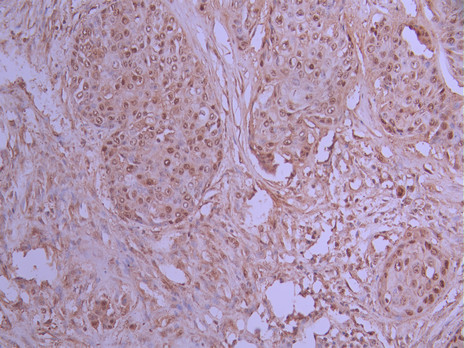

IHC image of CSB-RA912122A0HU diluted at 1:100 and staining in paraffin-embedded human pancreatic cancer performed on a Leica BondTM system. After dewaxing and hydration, antigen retrieval was mediated by high pressure in a citrate buffer (pH 6.0). Section was blocked with 10% normal goat serum 30min at RT. Then primary antibody (1% BSA) was incubated at 4°C overnight. The primary is detected by a Goat anti-rabbit polymer IgG labeled by HRP and visualized using 0.05% DAB.